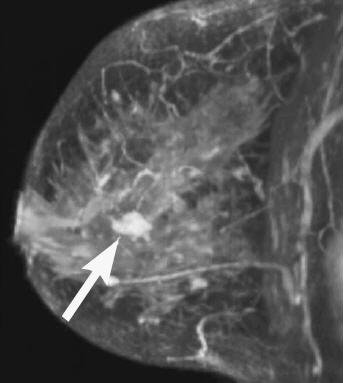

1981年7月2日

这是肿瘤外科学上里程碑式的事件。一直以来乳腺癌患者都需要接受根治性的乳癌根治术,这种传统的手术方式一直追溯到1882年Halsted的贡献,但手术创伤很大,副作用很多。在这一年的随机对照试验中,小于2 cm且淋巴结阴性的乳腺癌患者,研切除肿块所在的1/4象限乳房加上淋巴结清扫和放疗可以获得与乳腺癌根治术同等的疗效。肿瘤外科自此开始由巨创走向低创,而不是盲目扩大切除范围,开始重视了肿瘤生物学。